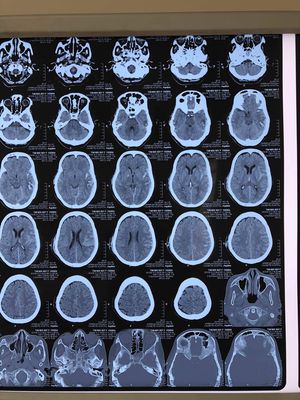

Tim Mik ,60yrs old Female, ID no: 150904 , calmette hospital ,2018.06.14 . What happened to protecting patients privacy ? Please edit and repost it .

Parece ser um trauma contuso em região temporal direita com contusão cerebral por contragolpe no lado esquerdo. Também apresenta fratura de esfenoide (ou zigomatico?) a esquerda, fratura de temporal esquerdo e direito